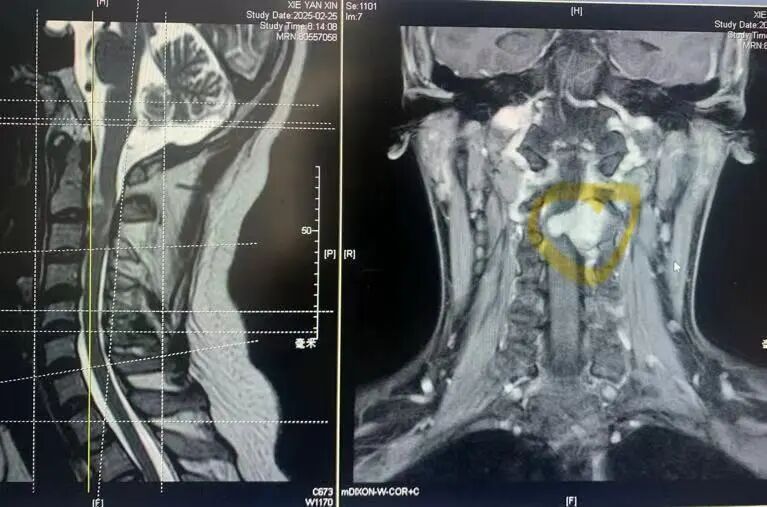

经过检查,他被诊断为颈2/3节段哑铃型神经鞘瘤,肿瘤严重压迫脊髓的右侧并从脊髓腹侧侵犯到左侧,随时可能造成不可逆的瘫痪。

高位颈2/3哑铃型肿瘤

从左侧经脊髓腹侧延伸到右侧压迫脊髓

手术后核磁共振证明肿瘤完全切除,脊髓恢复,没有脑脊液漏